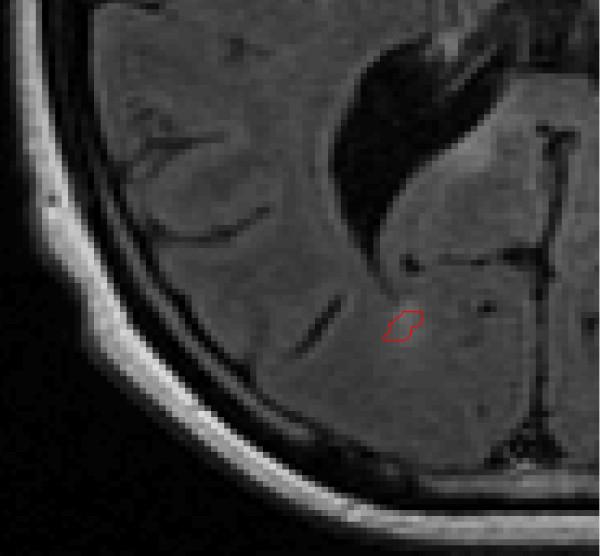

The MACC algorithm first identifies an outer bound for the solution path, forms a high number of iso-contour curves based on equally spaced contour values, and then selects the best contour value to outline the lesion. The MACC software was tested on a set of 17 FLAIR MRI images evaluated by a pair of human experts and a longitudinal dataset of 12 pairs of T2-weighted Fluid Attenuated Inversion Recovery (FLAIR) images that had lesion analysis ROIs drawn by a single expert operator.

In the tests where two human experts evaluated the same MRI images, the MACC program demonstrated that it could markedly reduce inter-operator outline error. In the longitudinal part of the study, the MACC program created ROIs on follow-up scans that were in close agreement to the original expert's ROIs. Finally, in a post-hoc analysis of 424 follow-up scans 91% of propagated MACC were accepted by an expert and only 9% of the final accepted ROIS had to be created or edited by the expert.